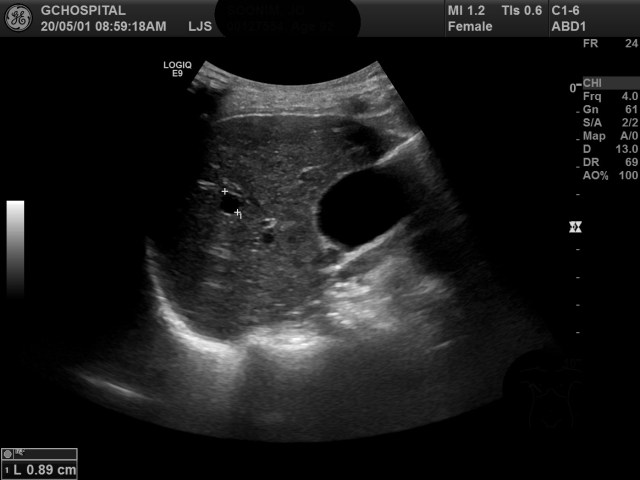

앞에서 병변 내부에 에코가 보였고, 후방에코강조소견이 보이지 않아 간혈관종의 가능성을 배제할 수 없었던 병변을 늑골사이로 탐촉자를 대어서 촬영한 영상입니다. Intercostal approach를 통해 해당 병변을 확인하면, 이렇게 내부에 에코가 전혀 존재하지 않는 무에코에 경계가 분명하면서 뚜렷한 후방에코강조소견을 확인할 수 있었습니다.

이 영상소견을 보고는 누구라도 이 병변이 단순낭종이라는 걸 의심하지 않겠죠. 늑골 밑으로 탐촉자를 대고 촬영하기만 하다보면, 이렇게 전형적인 단순낭종을 다른 병변으로 착각해서 쓸데없이 CT나 MRI같은 다른 영상검사를 추가하게 되는 경우가 생길수 있습니다. 사실, 현장에서 보면 이런 안타까운 사례들로 인해 의미없는 영상검사가 시행되는 사례들을 실제로도 가끔씩 보게 됩니다.

너무 뚱뚱하거나, 나이드신 분들은 간초음파영상을 촬영할 때 간혹 갈비뼈 사이로 탐촉자를 위치시켜 촬영하기가 어려울 때가 종종 있습니다. 그럼에도 불구하고 갈비뼈 사이로 접근해서 영상을 얻는 걸 포기하면 안되는 이유가 이런 일이 생기는 것을 막기 위해서입니다.